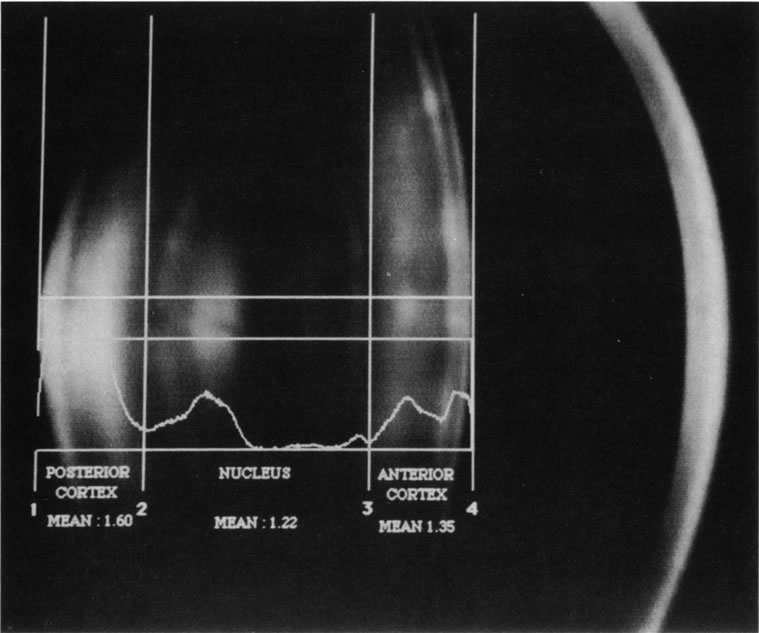

Fig. 6. Automated densitometric analysis of a digital Scheimpflug slit image of

a normal 50-year-old lens. Because of the characteristics

of the lens layers, the location of the cortex and nucleus can be automatically

detected by special software, and with automated densitometry, mean

optical density values can be easily and quickly obtained for

analysis. Thus, automated detection, classification, and grading may

be possible. Note the concentric layers of lens fibers in the cortex

and the nucleus.

Fig. 6. Automated densitometric analysis of a digital Scheimpflug slit image of

a normal 50-year-old lens. Because of the characteristics

of the lens layers, the location of the cortex and nucleus can be automatically

detected by special software, and with automated densitometry, mean

optical density values can be easily and quickly obtained for

analysis. Thus, automated detection, classification, and grading may

be possible. Note the concentric layers of lens fibers in the cortex

and the nucleus.